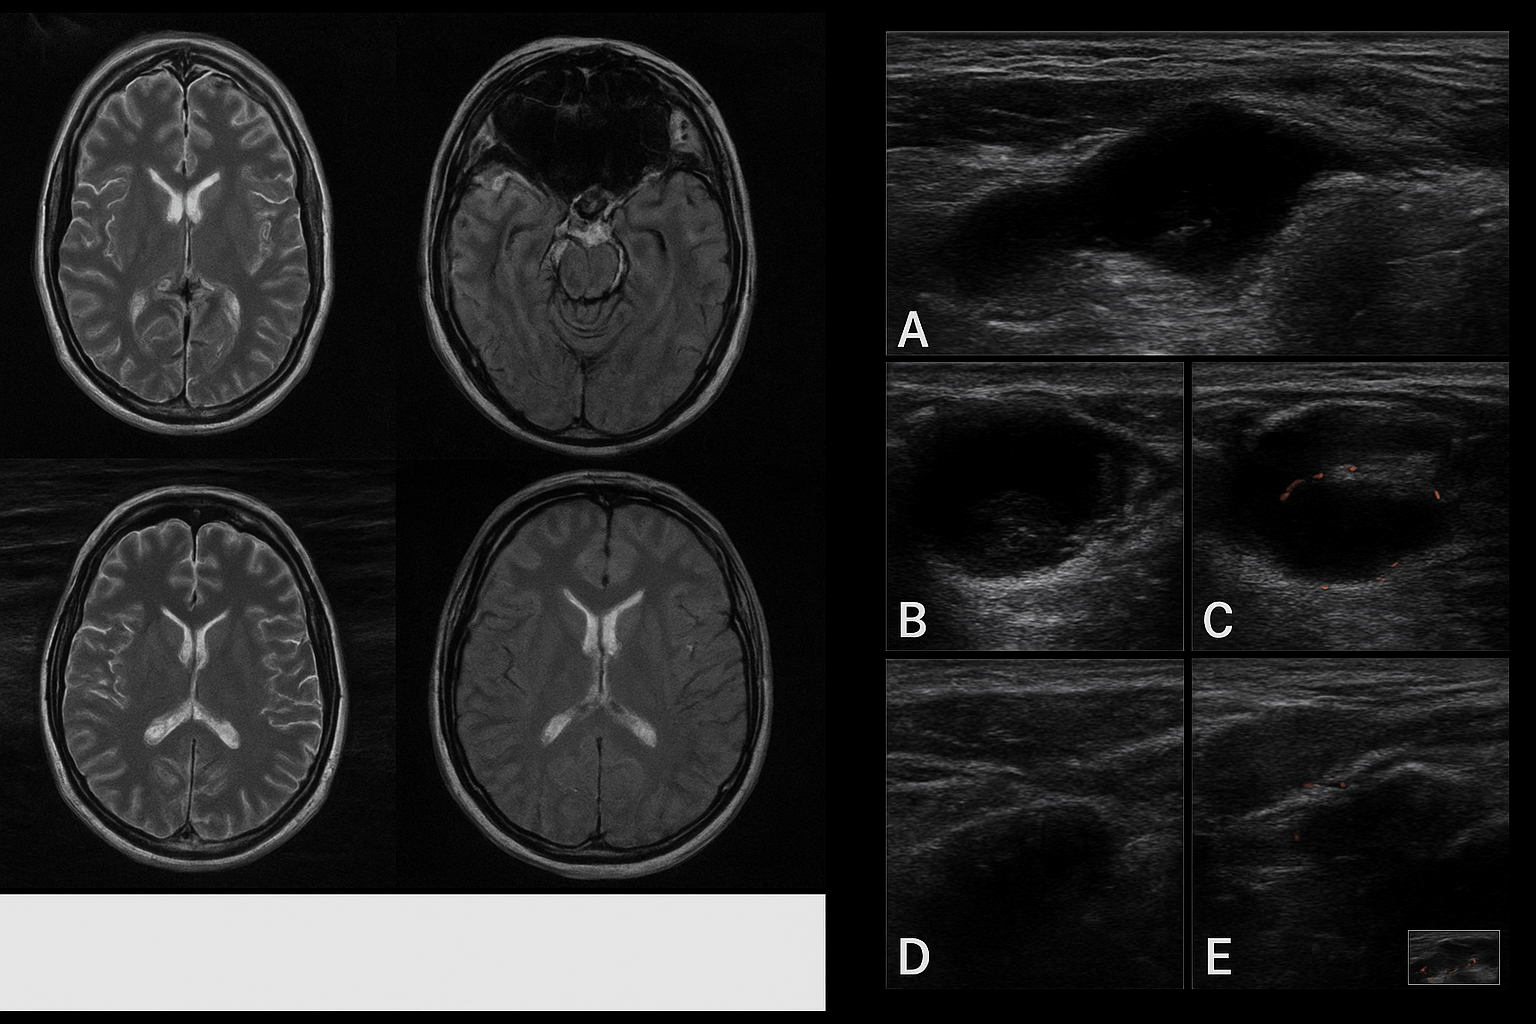

1. L’IRM « black-blood » pour les vascularites

Un des temps forts de cette édition sera la session intitulée Radiology Bootcamp prévue le 25 octobre, consacrée à l’imagerie des maladies auto-inflammatoires. Parmi les thèmes abordés : l’utilisation de l’IRM « black-blood sequencing » qui permet de mieux visualiser la paroi des gros vaisseaux chez les patients atteints de vascularites.

Toujours dans la même session, un cours intitulé Axial Imaging in Inflammatory Arthropathy : Distinguishing Degeneration from Disease met en lumière le défi suivant : différencier à l’imagerie les modifications « mécaniques/dégénératives » des signes d’« inflammation vraie ».

Concrètement, cela signifie pour le radiologue : adopter des séquences IRM ou échographiques plus sensibles à l’œdème osseux, à la synovite, mais aussi interpréter au-delà du cliché classique. Ce glissement ouvre la voie à une imagerie plus « rhumatologique » et spécialisée.

Le thème Reading the Crystals : Imaging Manifestations of Crystalline Arthropathies va explorer les formes d’arthrites liées aux dépôts de cristaux (goutte, chondrocalcinose…).

L’imagerie devient plus fine, plus ciblée : échographie haute résolution, scanner ou IRM adaptés aux dépôts, aux micro-calcifications. Pour un cabinet libéral, c’est une piste à envisager pour se différencier : proposer une expertise dédiée aux arthropathies à cristaux.